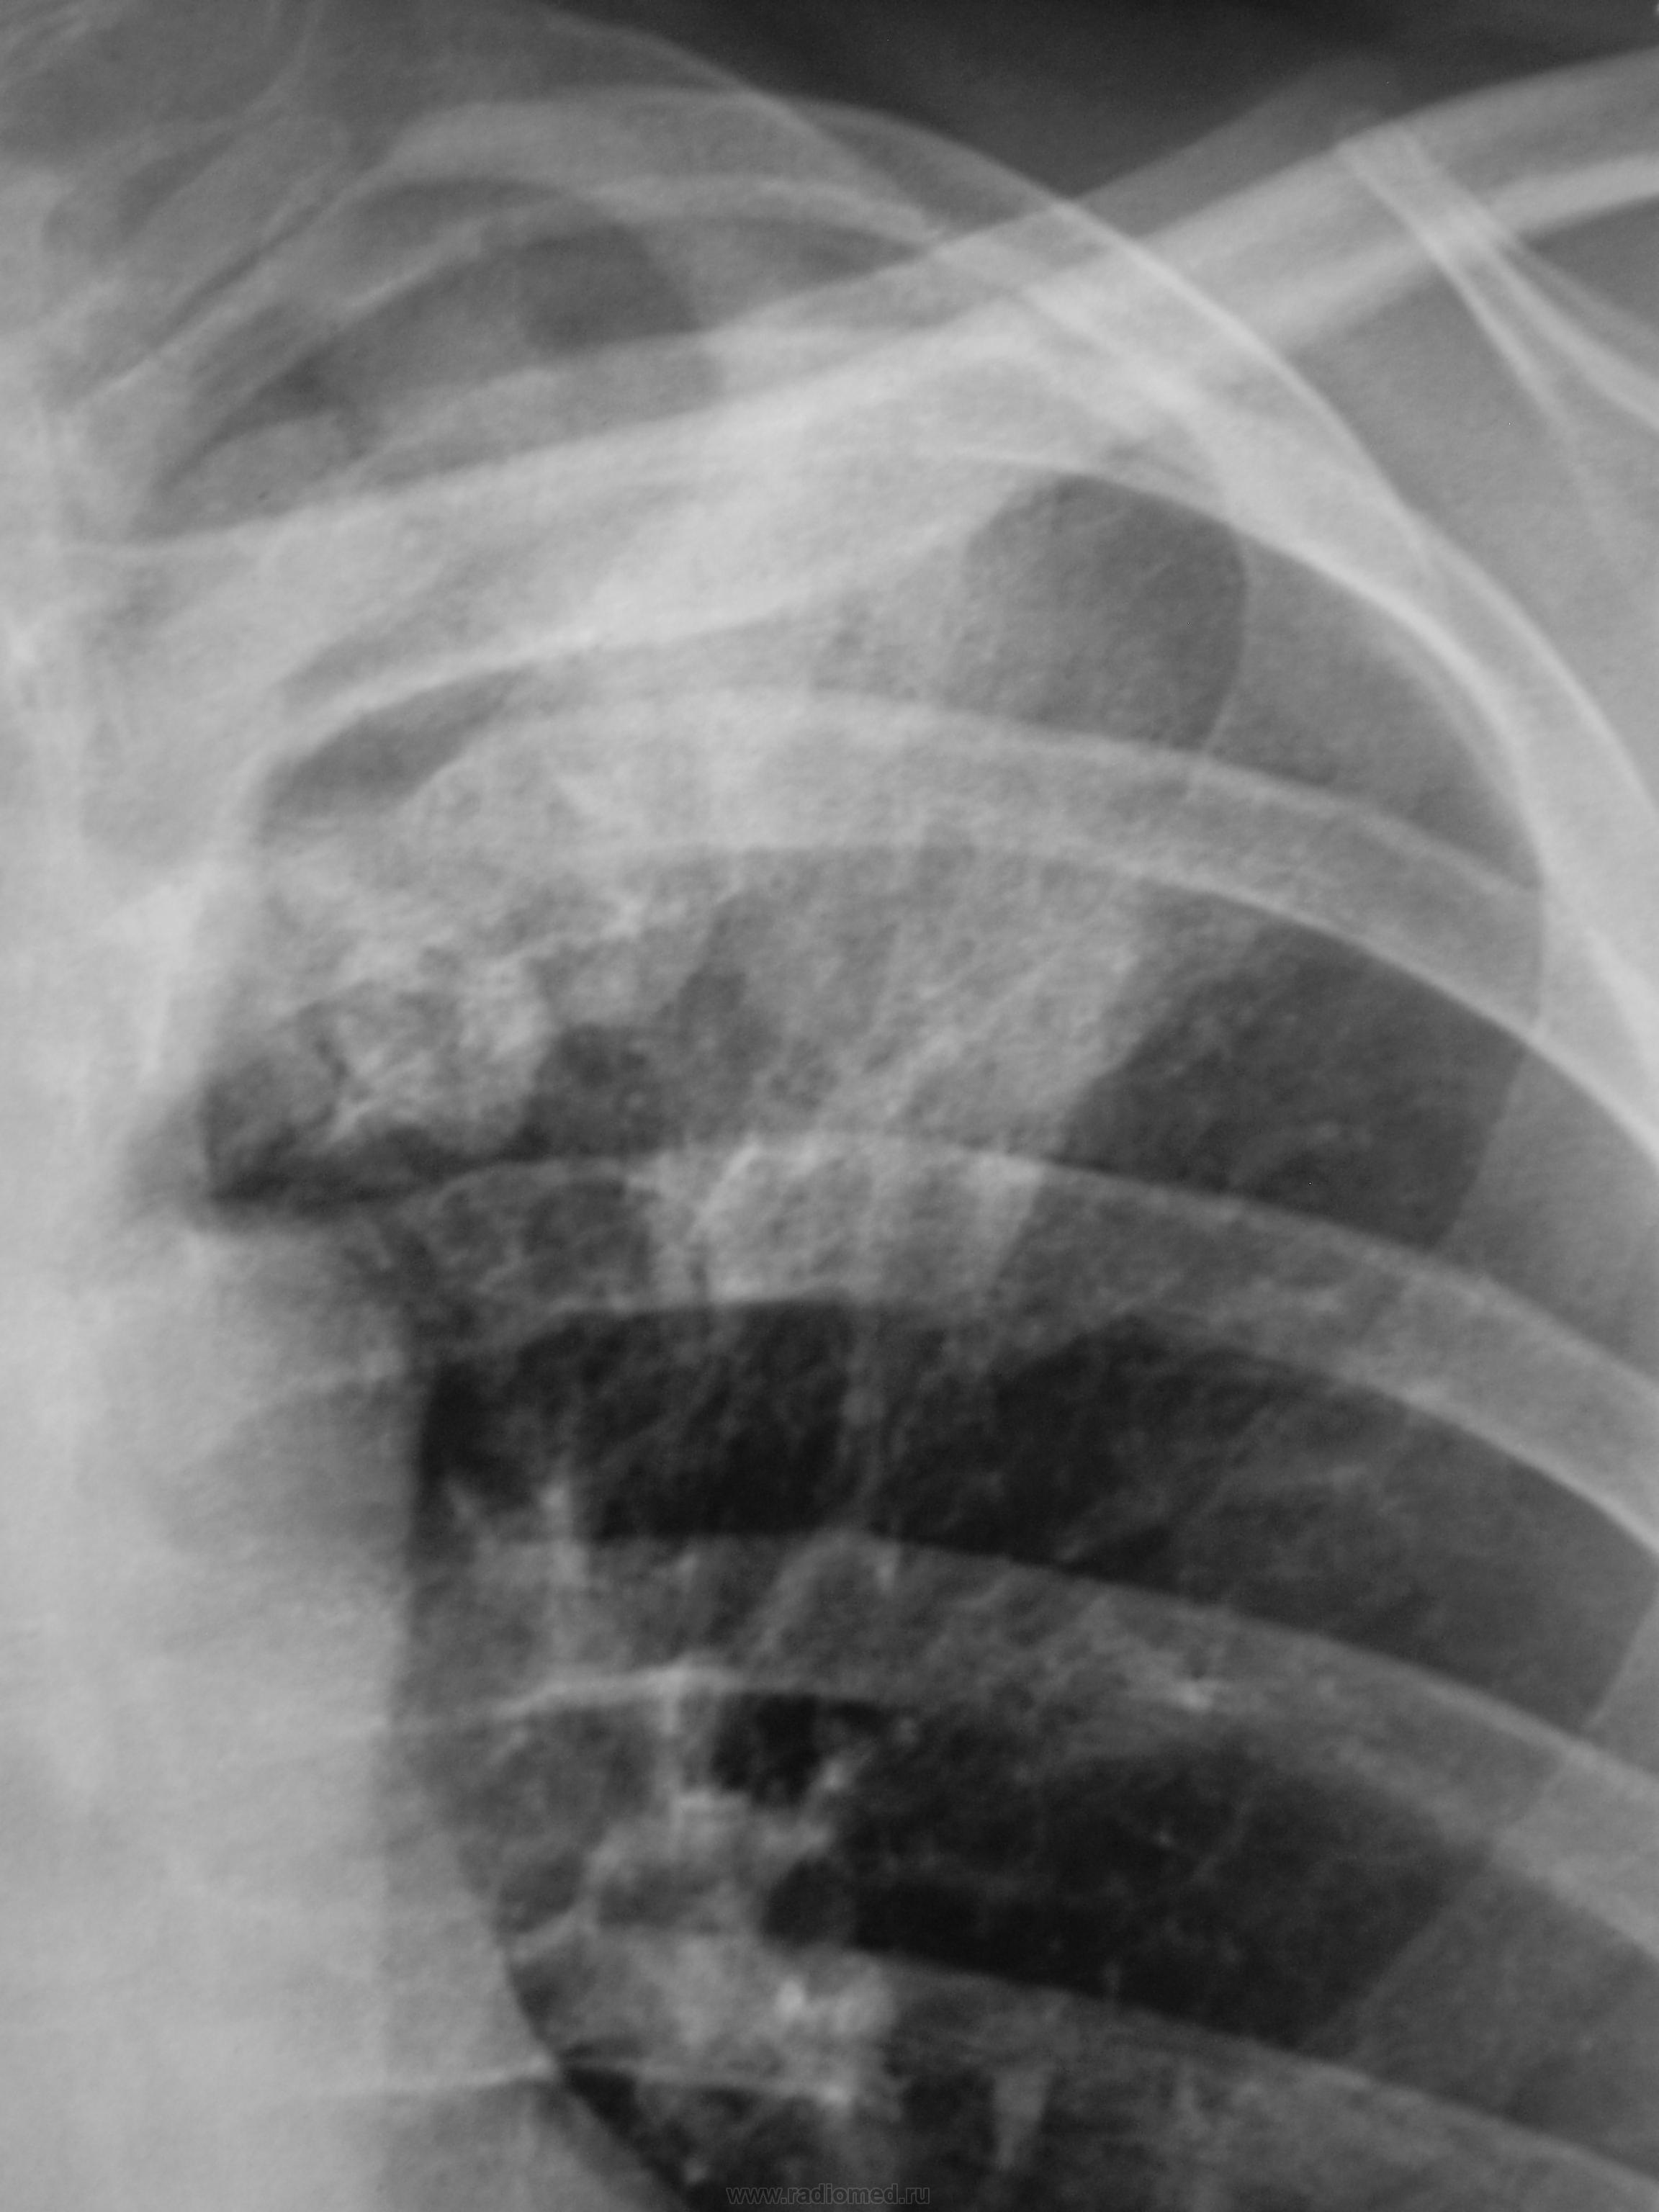

Лаборант флюорографа, сделав «флюшку», под «конвоем» привел пациента в рентгеновский кабинет.

Ваше мнение уважаемые коллеги.

тбц?

Наши  фтизиатры  написали бы пневмонию, противовоспалительную и т.д. терапию, а потом контроль, но в их учреждении. И они будут правы. А если я сам такое предложу -  буду недотепой. А вылезет рачок.

Я прикинул, описал скиалогию и в протоколе жестко порекомендовал, после проведения противовоспалительной терапии, обязательный рентген-контроль.

Через 10 дней после интенсивнейшей терапии – рентгенограммы